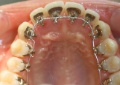

- Multiattache esthétique en technique linguale (face interne des dents): Technique WIN:

Les attaches d'orthodontie linguales sont placées sur la face interne des dents c' est à dire du côté de la langue ce qui les rend totalement invisibles. C'est une technique très intéressante chez l' adulte du fait de son invisibilité. Les attaches en alliage semi précieux sont individualisées pour chaque dent du patient ce qui les rend moins épaisses et plus confortables. Les empreintes pour la réalisation des attaches linguales sont réalisées à l'aide du scan intra-oral TRIOS 5 de chez 3Shape.